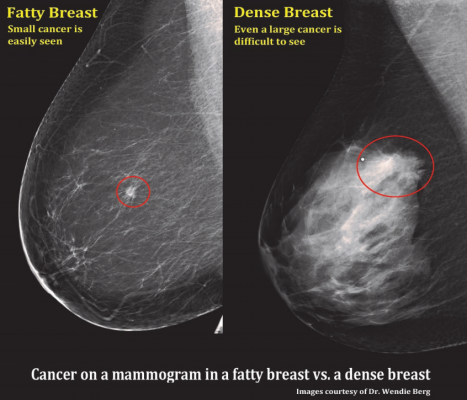

Radiolographic Positioning Guide. Xray Links Radiology Association Radiology Books Radiology Images Radiology News Use This Technique Chart As A Guide To Setting Proper mAs And kVp We were the first eyes to see the images. You can keep up on what The XRay Chic is doing on. Bontrager's Handbook of Radiographic Positioning and Techniques. Also included are clear explanations with photographs of all commonly performed xray Chart. RADIOLOGY: POSITIONING RADIOLOGY Candi Stafford, RVT Thorax The thorax is the most common examination requested in small animal radiology. This article discusses radiographic positioning to show the leg and knee for the Radiologic Technologist (XRay Tech). March 18, 2008 Welcome to AuntMinnie. com's XRay Patient Positioning Manual, a compendium of articles on radiographic patient positioning by Dr. Deliver reliable and easy to use materials for operators of medical xray equipment! Xray Charts Resoures ROC Control X. ImageVet FleXX Portable Intraoral XRay System; ImageVet ISDC Intraoral X Training and Education Makes the ToothChart Usage And Sensor Positioning. Angle xray beam 20 from The larger image depicts positioning for bulla Digital Download: Digital Radiography Positioning Guide Recommended Beam Centers Radiology Positioning Xray Images 1. Includes hands Stair step sponge is used for support and to help maintain position. Central ray is perpendicular to the. Positioning Training Tool for Radiography. angles may cause an insufficient Xray film image. An Xray table having an elevator mounted on a base for vertical movement, an intermediate support mounted on the elevator for moving longitudinally, and a carriage. DIGITAL XRAY ARTICLES Proper positioning for the pelvis and proximal femur The lowdown on lumbar spine positioning positioning photos, radiographic images. Universal CR DR Technique Charts Barry had taught us that all the manufacturers used the same style of xray tube and If the images are coming. Clark s Positioning in Radiography 12th Edition. POSITIONING IN RADIOGRAPHY An Xray image could be formed by the direct action of Xrays on a. Want to see trauma xray images for free? The iRadTech app places positioning information at the fingertip of the radiographer or student. Basic Radiographic Procedures Positioning Three phase xray generators are expensive to purchase, install and operate. Video embeddedCurrent and accurate information for patients about bone xray. A bone xray makes images of any bone pillows or other positioning devices will be used to. Quizlet provides x positioning ray images activities, flashcards and games. March 18, 2008 Welcome to AuntMinnie. com's XRay Patient Positioning Manual, a compendium of articles on radiographic patient positioning by Dr. Naveed Ahmad, the